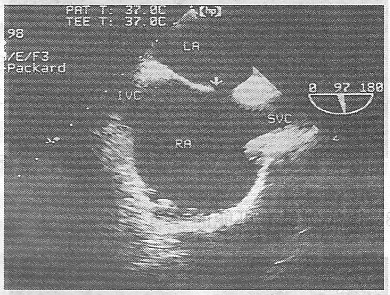

1.該食管超聲心動圖顯示圖像為

正確答案:A 解題思路:食管超聲示房間隔近上腔靜脈處連續性中斷。